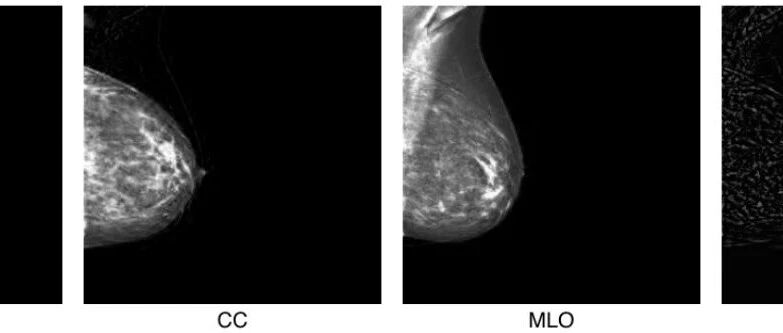

墨西哥理工新招:用RGB三通道“打包”双视图,AI一键生成乳腺钼靶图